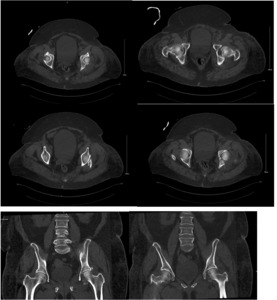

A 64-year-old female with diabetes, hypertension, and dyslipidemia was involved in a motor vehicle accident, resulting in significant injuries. She presented to the Emergency Department via Medivac and underwent a comprehensive trauma assessment. Orthopedic evaluations reveal a fractures dislocation of the left acetabulum with a posterior wall fracture and a femoral head fracture (Figure 1. Figure 2, Figure 3). Additionally, a minimally displaced fractures of the left tibial plafond was identified. Due to the complexity of her injuries and considering her age, a surgical plan was formulated for fixations of the acetabular and femoral head fractures, along with total hip replacements on the left side, and fixations of the tibial plafond fractures. After induction of general anesthesia and regional block, the patient was positioned in lateral decubitus for the hip procedures. Utilizing the Kocher-Langenbeck approach, the posterior wall fracture was stabilized with lag screws and a buttress plate (Figure 4A, 4B). The hip was then dislocated, the femoral neck cut, and the acetabulum reamed. A Stryker Trident cup size 46 was inserted for a press-fit, augmented with three screws, and a metal liner for dual mobility was added. Subsequently, the femur was broached, and an Accolade stem size 2 with a double head was implanted, ensuring excellent stability and appropriate legs length (Figure 4C). The operation concluded with thorough irrigation and closure in layers. The patient was then repositioned supine to address the tibial plafond fracture, which was stabilized with a single medial plate, followed by application of a dry dressing and a below-knee backslabs. Postoperatively, the patient experienced mild pain but was otherwise stable. Dressings on the left hip and ankle were intact, with ankle motion preserved and a palpable dorsalis pedis pulse. She began mobilization with physiotherapy from day one and showed no active complaints throughout her recovery, proceeding smoothly until discharge (Figure 5).